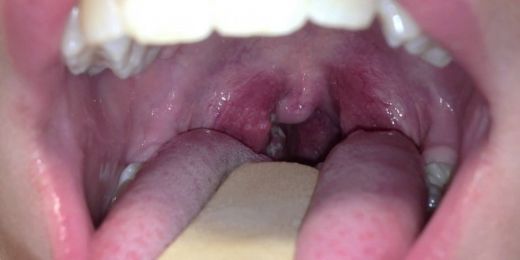

Bademcik şişmesi, tıpta "tonsillit" olarak adlandırılan bir durumu ifade eder ve bademciklerin iltihaplanmasıyla karakterizedir. Bu durum, çeşitli etkenler nedeniyle ortaya çıkabilir ve genellikle boğaz ağrısı, yutkunma güçlüğü, yüksek ateş gibi belirtilerle kendini gösterir. Bademcik şişmesi tedavisinde ilaç kullanımı önemli bir yer tutmaktadır. Bu makalede, bademcik şişmesi için ilaç kullanımının faydaları, türleri ve dikkat edilmesi gereken noktalar üzerinde durulacaktır. Bademcik Şişmesinin Nedenleri Bademcik şişmesinin birçok nedeni olabilir; bunlar arasında:

Bademcik Şişmesi Belirtileri

Bademcik şişmesi genellikle boğazda ağrı, yutkunmada zorluk, öksürük ve bazen ateş gibi belirtilerle kendini gösterir. Bu belirtiler, günlük yaşamı oldukça zorlaştırabilir ve rahatsız edici bir durum yaratabilir.